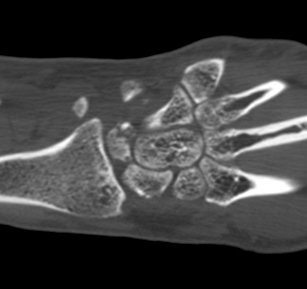

ÃÊÀ½ÆÄ°Ë»ç : ¼Õ¸ñ ¹èÃø Á¾´Ü¸é°Ë»ç¿¡¼­ ¼ö±Ù°üÀý³» ¼ö¾×Àú·ù°¡ °üÂûµÊ(»çÁø 1).

¼Õ¸ñ ÀåÃø Á¾´Ü¸é°Ë»ç¿¡¼­ ¿ù»ó°ñ °ñ±ØÀÌ °üÂûµÊ(»çÁø 2).